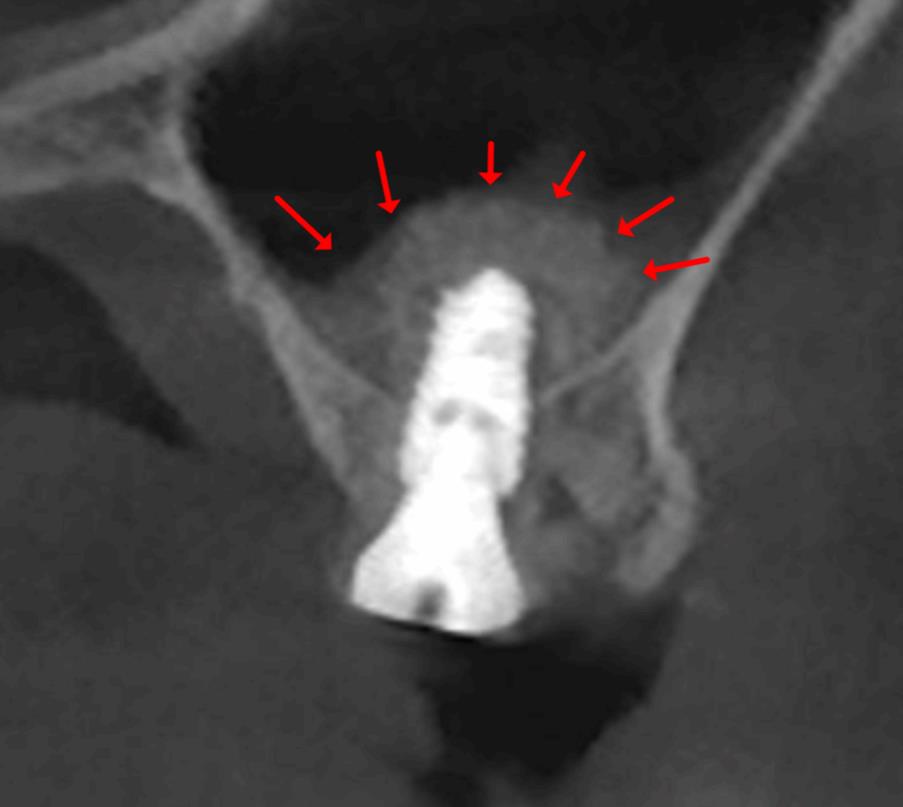

“잇몸이 치아 안으로 자라 들어왔어요…” 발치 선고받을 뻔한 치아, 잇몸 수술과 레진 벽(Wall)으로 살려낸 과정